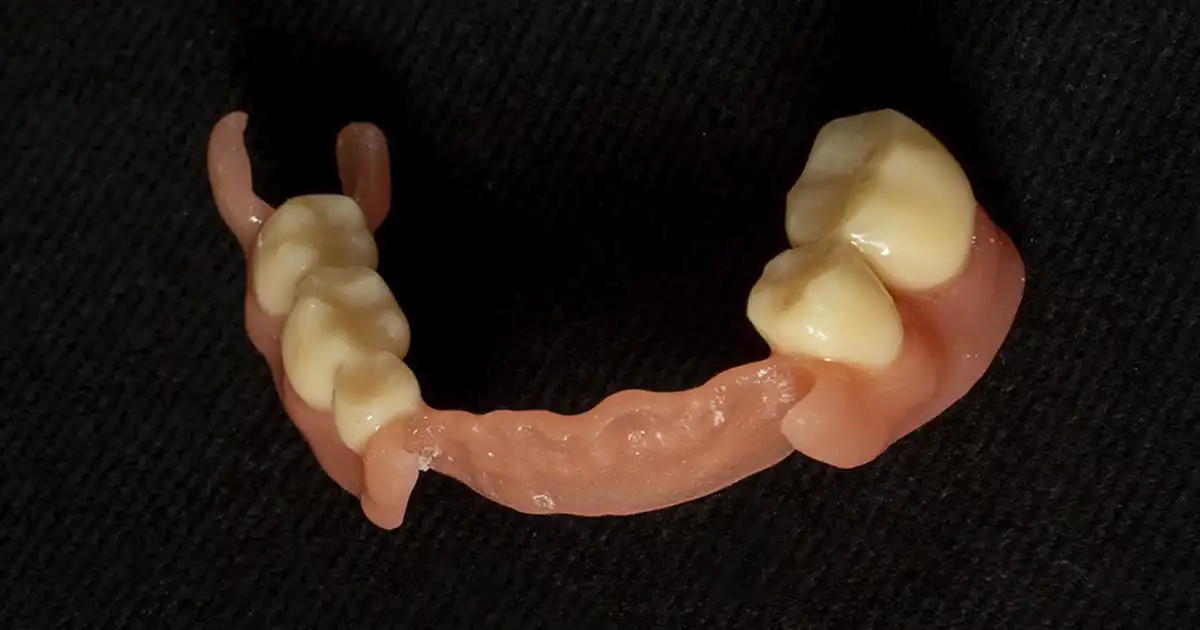

Prótesis flexible digital

Caso clínico de prótesis flexible digital orientado a recuperar función masticatoria, soporte, estabilidad y estética en paciente con pérdida dentaria parcial o total